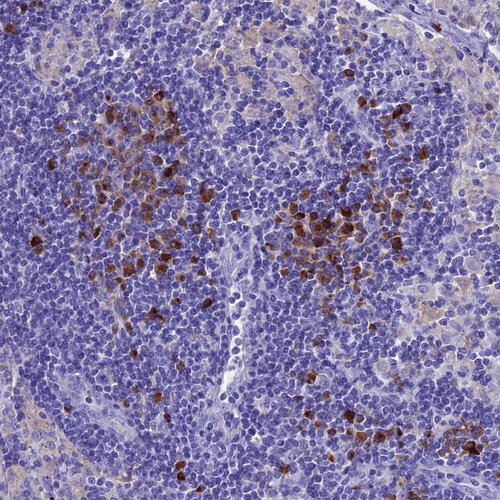

Immunohistochemical staining of human lung shows strong cytoplasmic positivity in macrophages.